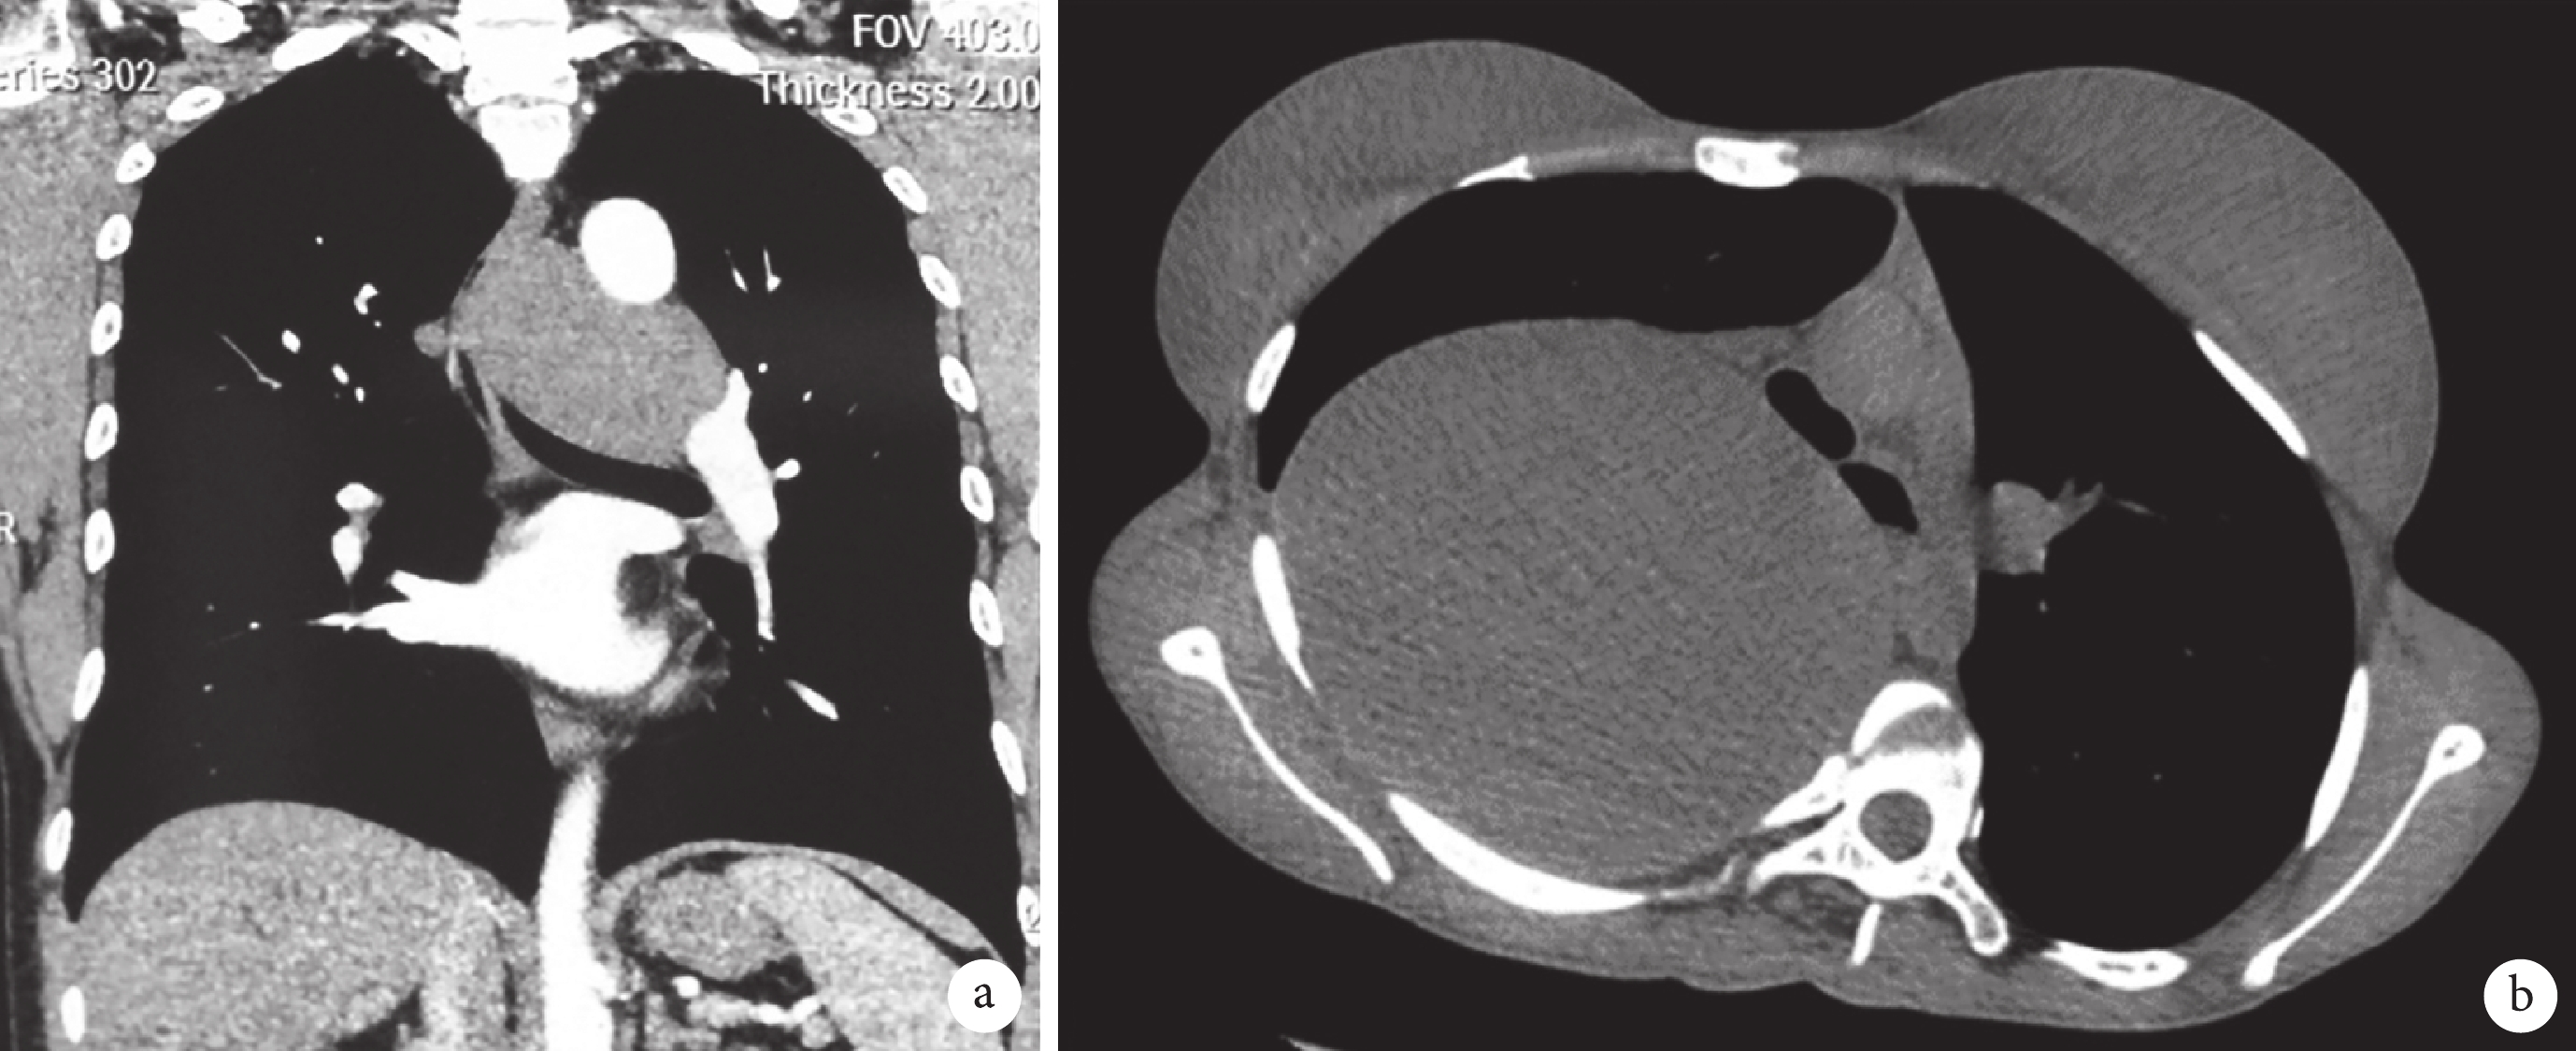

支氣管源性囊腫起源妊娠期第 26~40 d 的原始腹側前腸的異常萌芽,發病機制尚不明確,可發生于縱隔的任何部位[3-4]。支氣管源性囊腫并無特異性臨床表現,以壓迫癥狀為主,如咳嗽、胸悶、胸痛、吞咽困難等,合并感染者可出現發熱或胸腔積液[3-5]。文獻報道 9%~67% 的縱隔支氣管源性囊腫存在癥狀[4-5],部分無癥狀患者隨年齡增長,囊腫逐漸增大可出現癥狀[6],本組 34.4%(11/32)有癥狀患者為觀察期間出現(圖 1a),囊腫直徑最大可達 22.0 cm(圖 1b)。因此,支氣管源性囊腫有增大、進展的可能。

a:合并胸悶癥狀的縱隔支氣管源性囊腫 1 例;b:巨大縱隔支氣管源性囊腫 1 例